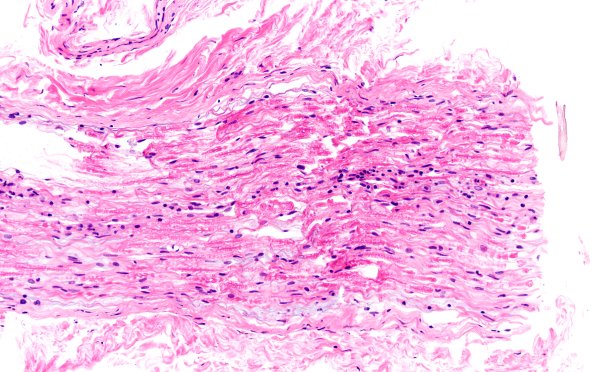

Washington University Experience | PERIPHERAL NEUROPATHY | 7B CIDP | 4A CIDP (Case 4) D Anterior Interosseus nerve H&E 20X

Case 4 History ---- The patient is a 63-year-old female with type 2 diabetes and a several month history of progressive upper and lower extremity weakness and sensory loss in the arms and legs, changes in voice and difficulty swallowing. There was clinical concern for a demyelinating process like CIDP. Operative procedure: Right nerve to flexor digitorum superficialis biopsy; right quadriceps biopsy; right anterior interosseous nerve (AIN) biopsy; right deltoid muscle biopsy. ---- 4A This is a longitudinal section of the anterior interosseus nerve showing perivascular inflammation. (H&E)